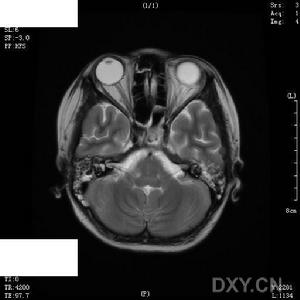

小兒病毒性腦炎--影像1.嗜睡